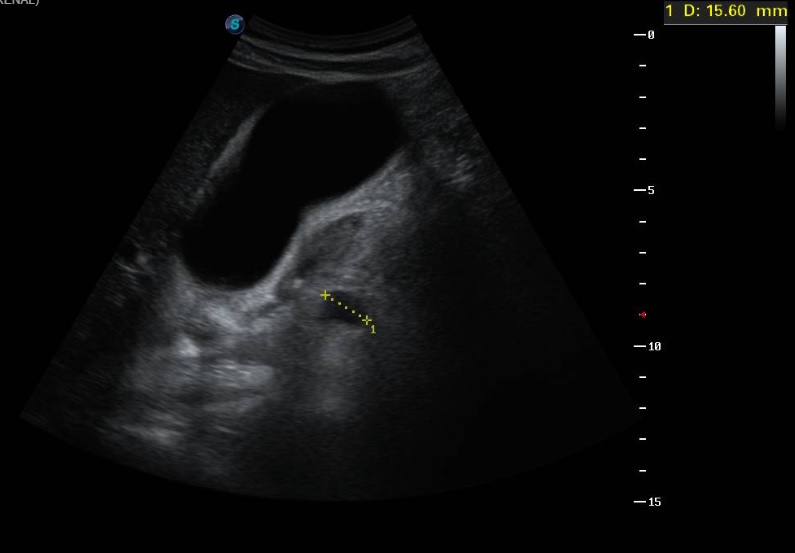

Ecografía clínica a pie de cama: Parénquima hepático y esplénico de ecoestructura preservada. Vesícula biliar marcadamente distendida con imagen hiperecogénica de 2 cm en porción declive compatible con litiasis. Dilatación de la vía biliar intrahepática difusa así como dilatación del colédoco.

La litiasis y la dilatación de la vesícula biliar encontrada en la ecografía clínica no justificaba todo el cuadro, por lo que solicitamos ecografía reglada al equipo de radiología. En ella informan marcada dilatación de la vía biliar intrahepática, con un colédoco de hasta 15 mm, y estructura mamelonada de aproximadamente 7 cm en cabeza pancreática. Se completa estudio con Tomografía Axial Computarizada que confirma masa en cabeza pancreática compatible con adenocarcinoma que condiciona dilatación de la vía biliar retrógrada.